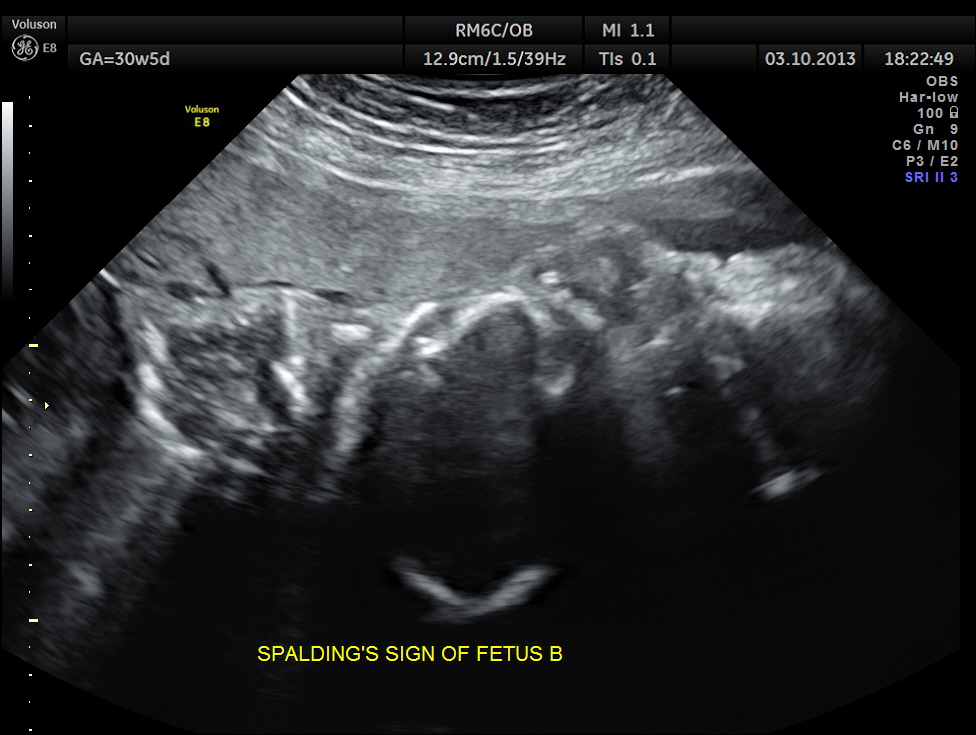

Intra uterine fetal death of the 2nd fetus was seen – Overlapping skull bones and maceration of fetal parts, with absent cardiac activity.

The overlapping skull bones of the fetus ,which died earlier .